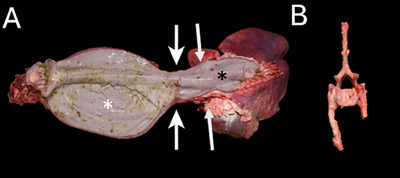

一个4岁的尼日利亚侏儒提出慢性反流和颈部肿胀的三年持续时间。体格检查发现颈部腹侧有一个大肿块。山羊多次尝试吞咽和反刍,但肿块的大小没有明显变化。颈椎x线片显示食道节段性扩张至胸入口水平。CT显示过渡性第七颈椎伴左右肋骨融合,导致食管外压迫和胸入口水平梗阻。这是山羊颈肋引起食管肥大的第一个报告。

A 4-year-old Nigerian Dwarf wether presented for chronic regurgitation and cervical swelling of three years duration. Physical examination revealed a large ventral cervical mass. The goat made repeated attempts to swallow and regurgitate, but the mass did not change significantly in size. Cervical radiographs revealed segmental esophageal dilation to the level of the thoracic inlet. CT revealed a transitional seventh cervical vertebra with fused right and left ribs, resulting in extramural esophageal compression and obstruction at the level of the thoracic inlet. This is the first report of a cervical rib causing megaesophagus in a goat.